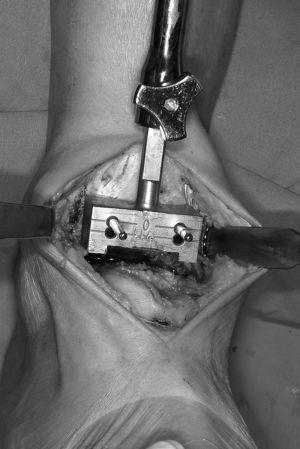

Figura 4. Introducción del componente intermedio móvil. Los componentes tibial y astragalino ya han sido implantados.